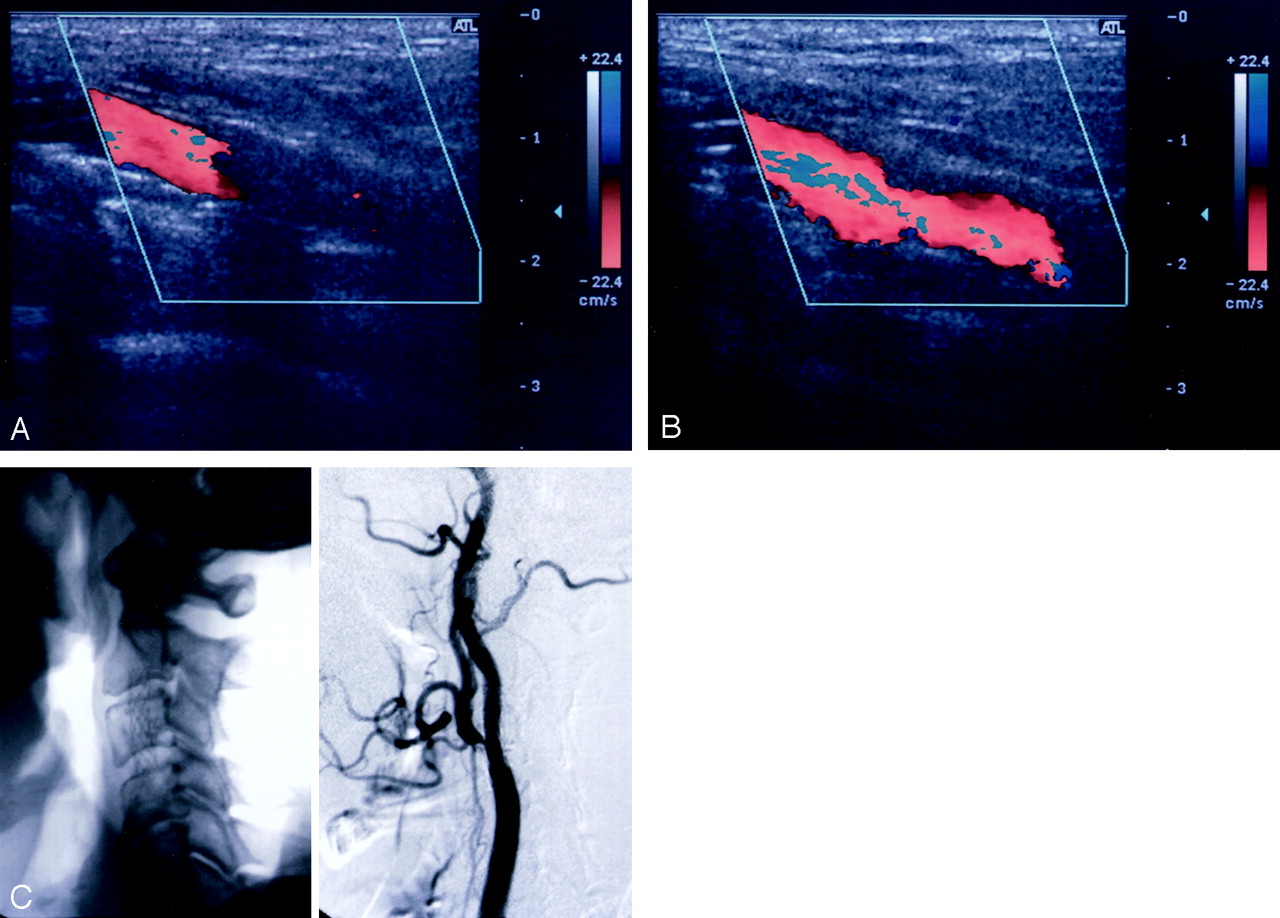

In five of the 13 patients who underwent CS placement with a single stent, the CCCD image and the CE-CCCD image differed significantly in the visualization of the entire length of the flow in the stent. These five patients had high carotid lesions (Fig 2). In the nine patients whose stent was located below the level of the second vertebra, nonenhanced CCCD images allowed full confirmation of stent patency (Table). With CE-CCCD sonography, improvement in the visualization of blood flow in a stent did not depend on the stent material (Table). In patient 4, an asymptomatic intimal hyperplastic narrowing of approximately 50% of the lumen was confirmed by means of DSA after successful CS placement. However, this intrastenotic residual lumen could not be visualized on the CE-CCCD images, although a more color-coded stream was shown proximal and distal to the stenotic portion.

Benefit of CE-CCCD sonography in a patient with a high cervical lesion (patient 5).

A, Nonenhanced CCCD image allowed visualization of only the proximal half of the stented lumen.

B, After the application of the contrast agent, flow in the distally positioned stent could fully be detected by means of CE-CCCD imaging.

C, Corresponding lateral X-p (left) and DSA (right) images.